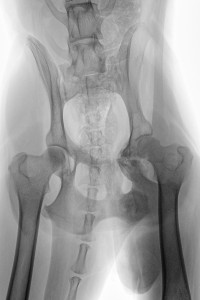

Auf der RÖ-Aufnahme vom 06. Jan. 2016 ist eine deutliche Kallusbildung an allen Frakturstellen zu erkennen. Wir machten uns allerdings Sorgen, dass es zu einer überschießenden Kallusreaktion am caudalen Bereich des Acetabulums kommen könnte, die dann die Bewegung des Femurkopfes einschränken könnte. Ab Januar wurde die Physiotherapie / Unterwasserlaufband dann zwei Mal wöchentlich durchgeführt und zu Hause mit isometrischen Übungen (wie Trampolin-Wippen, auf 3 Beinen stehen, Podesttraining usw.) begonnen, um die immer noch schwachen Oberschenkelmuskeln zu trainieren. Gleichzeitig haben wir das Ergodyn Gerät jeden zweiten Tag eingesetzt, mit längerer Anlegezeit (ca. 15-20 Min.).

Die letzte RÖ-Kontrolle habe ich am 03. Feb. gemacht und da die Kallusbildung bis dahin weitestgehend abgeschlossen war und der Orthopäde uns grünes Licht gegeben hatte, habe ich Ihr Therapiegerät daher ausschleichend benutzt, d.h. etwa 3 Mal pro Woche für 15 Min.